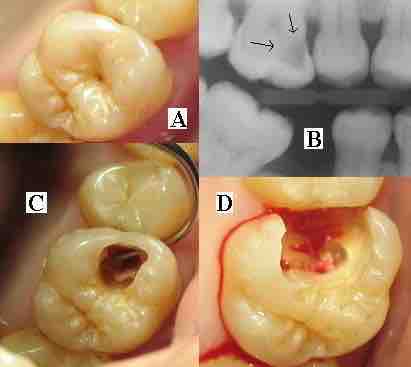

As the enamel and dentin are destroyed, the cavity becomes more noticeable . The affected areas of the tooth change color and become soft to the touch. Once the decay passes through enamel, the dentinal tubules, which have passages to the nerve of the tooth, become exposed, causing a toothache. The pain may worsen with exposure to heat, cold, or sweet foods and drinks. Dental caries can also cause bad breath and foul tastes. In highly progressed cases, infection can spread from the tooth to the surrounding soft tissues. Complications such as cavernous sinus thrombosis and Ludwig's angina can be life-threatening.

Dental caries

(A) A small spot of decay visible on the surface of a tooth. (B) The radiograph reveals an extensive region of demineralization within the dentin (arrows). (C) A hole is discovered on the side of the tooth at the beginning of decay removal. (D) All decay removed.